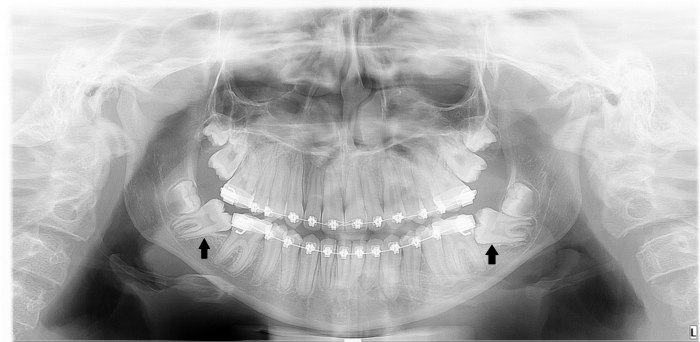

Rx Panorâmico - Pré cirúrgico, com os elementos 37 e 47 impactados - Clínica Cliniface

Rx Panorâmico - Pré cirúrgico, com os elementos 37 e 47 impactados